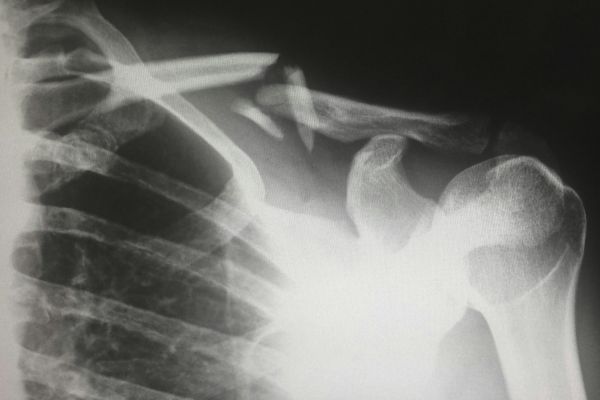

Речь идет о мобильном аппарате MATRIX HP 32, которым пользовались медики филиала на ул. Балтийской, 4а. Как оказалось, эксплуатация, хранение рентгеновского источника ионизирующего излучения осуществлялись без соответствующего санитарно-эпидемиологического заключения.